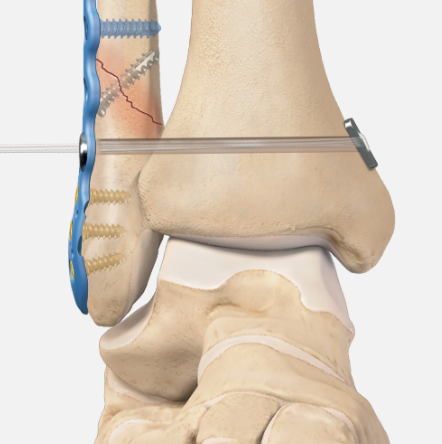

Management

ORIF fibular

Syndesmosis reduction and stabilization with plate versus screws

Reduction syndesmosis

Avoid malreduction

- arthroscopic visualization

- open reduction of syndesmosis via anterolateral approach

Vumedi open reduction syndesmosis

Foot in neutral

- clamp across medial and lateral malleolus

- don't reduce in plantarflexion as posterior talus is more narrow

- don't over reduce the joint

- check symmetrical joint space on mortise view